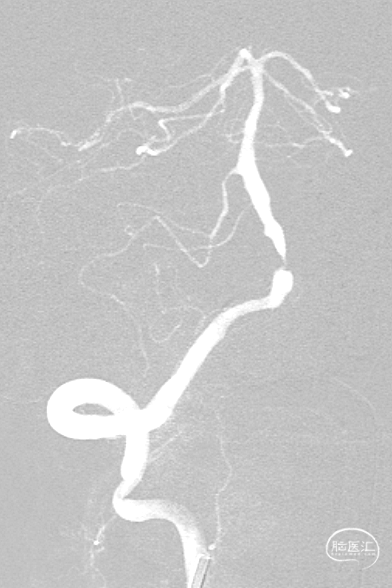

超选右侧椎动脉造影:右侧椎-基底动脉连接处次全闭塞,前向血流 mTICI 2b级。

最后影像:椎基底动脉连接处残余狭窄约20%,前向血流改善明显,mTICI3级。远端各血管显影良好,分支较术前增多。

半年后复查造影:支架内无明显再狭窄。椎基底动脉通畅,前向血流mTICI3级。